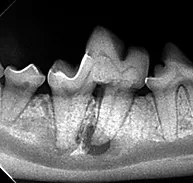

Dental care is essential to an animal’s overall health. Knowing how to properly identify and treat oral disease is crucial in the well-being of your patients. The American Veterinary Dental Society has reported that the majority of cats and dogs have periodontal health issues by the age of three. Many oral problems are not visible above the gum-line and can be overlooked without the right education. Untreated or misdiagnosed dental problems are the source of chronic pain and infection.